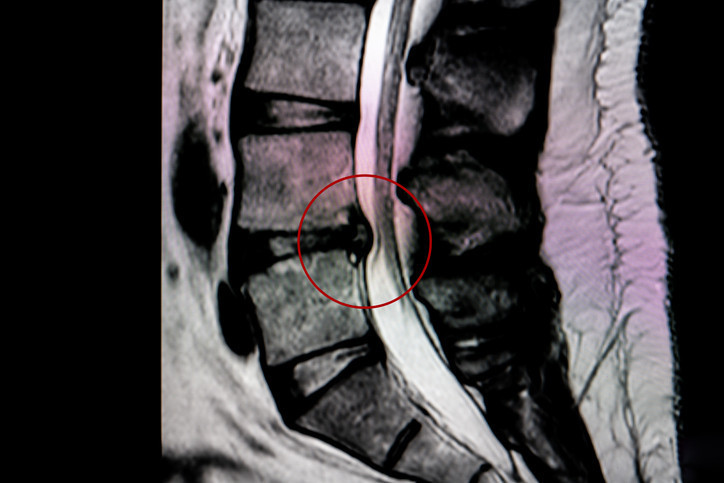

“Ayaklarda uyuşma, yürüme ve oturmada güçlük çekilmesi bel fıtığının habercisi olabiliyor. Eğer hastalık ilerlerse idrar kaçırma, cinsel fonksiyon kayıpları ve hatta yürüyememe gibi çok daha ağır tablolarla karşılaşılabiliyor. Bu belirtiler görüldüğünde vakit kaybetmeden bir uzmana başvurulmalı ve özellikle MR görüntüleme ile bası derecesi belirlenmeli.”